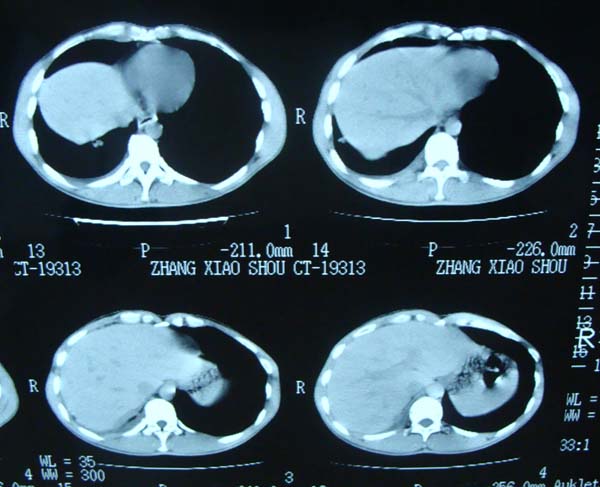

标题: CT15132:男,26岁。建筑混凝土工人。发热。咳。 [打印本页]

标题: CT15132:男,26岁。建筑混凝土工人。发热。咳。

右肺继发型肺结核,右侧胸腔积液、胸膜肥厚粘连。

右肺继发型肺结核,右侧胸腔积液。

继发结核并胸水

胸膜肥厚

年轻男性,右肺多形性病灶伴右侧胸腔积液,考虑结核

右肺继发型肺结核,右侧少量胸腔积液、胸膜肥厚。